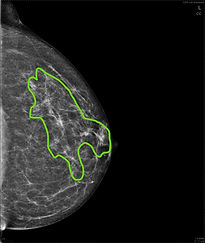

Here are examples of breasts with less white glandular tissue.

These women have NON-DENSE breast tissue. The areas of white are outlined below. You can see that there is less white glandular tissue than on the examples above.